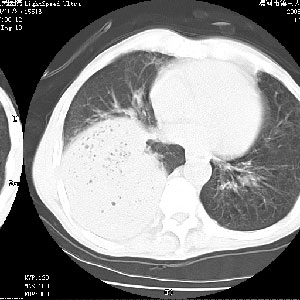

病变按肺叶分布,病变内可见多个小空腔影,未见充气支气管影,中间段支气管管腔肺窗示密度欠均匀,下肺支气管分叉处基底段支气管隐约可见,未见明显狭窄,中叶支气管通畅,

考虑:阻塞性肺炎伴小脓肿形成可能性大。(痰栓可能性大)

右下肺实变,内有弥漫分面小气泡而无支气管征,叶间裂前移,呈臌大之形,而无收缩之状,兼纵隔稍左行移,故。不支持不张,倒支持大叶肺叶,如楼上所说,小气泡不象残留之肺,不可以考虑产气菌感染吗。

阻塞性肺炎,肺脓肿形成。依据,右下支气管不通,大片实变形内可见小气泡。不支持肺不张。